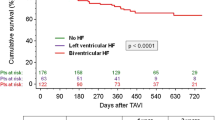

A total of 125 CF-LVAD patients with none or trivial preoperative AI were enrolled, and their characteristics are summarized in Table 1. Age was 43 ± 14 years, 87 (70%) were male, and BSA was 1.61 ± 0.20 m2. During the study period, 16 patients died, 40 underwent heart transplantation after 33 ± 11 months of waiting, and 7 underwent CF-LVAD explantation. During the 30 ± 16 months of CF-LVAD support, survival rate was 93% at 1 year and 89% at 2 years (Supplemental Fig. 1).

Preoperative AI grade was none in 86 (69%) and trivial in 39 (31%) patients. During 20 ± 14 months of echocardiographic follow-up, 32 patients developed de novo moderate or severe AI after CF-LVAD implantation. The rate of freedom from de novo AI was 86% at 1 year and 67% at 2 years.

Multivariable analysis showed that higher preoperative RVSWI [hazard ratio (HR), 1.12 /g/m2/beat; 95% confidence interval (CI), 1.00–1.20 /g/m2/beat; p = 0.047] and preoperative trivial grade AI (HR, 2.8; 95% CI, 1.2–6.4; p = 0.020) were independent risk factors for de novo AI (Table 2). In the present cohort, the median RVSWI value was 6.8 g/m2/beat and rate for freedom from de novo AI was significantly higher in patients with preoperative RVSWI < 7 g/m2/beat (p = 0.03) (Fig. 2).